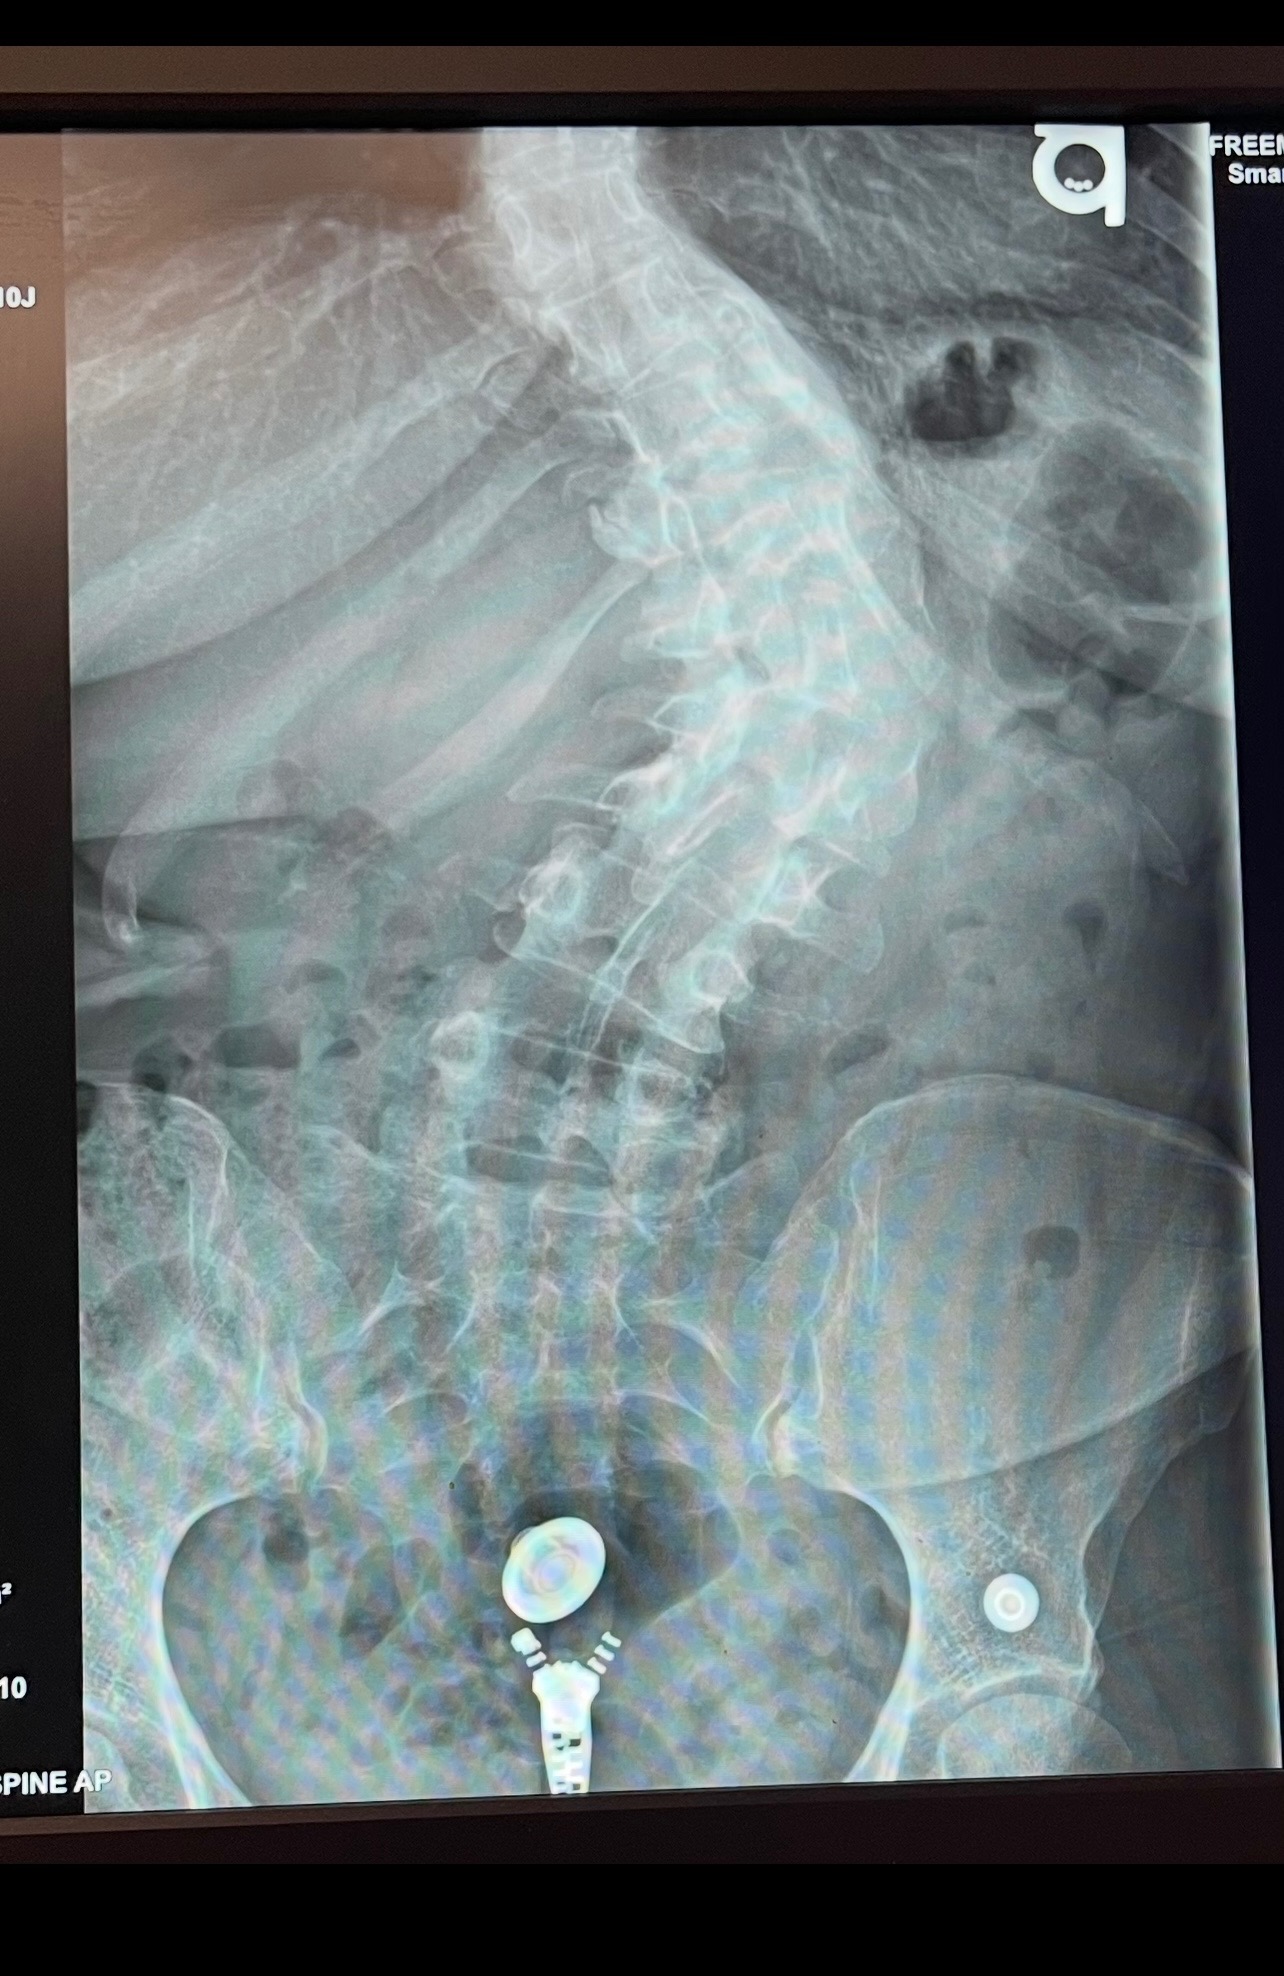

Hello, I’m Rachel and I’m having surgery to correct my severe scoliosis in early October.

Life happened, and I didn’t have the capability to get help. Unfortunately, the pain got to a point where getting help was the only option. I’ve had X-rays and MRIs and quit smoking. I’m doing all the things to make sure this is a success!